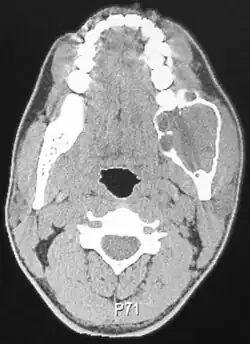

Radiograficamente, o ameloblastoma se apresenta como uma lesão radiolúcida uni ou multiloculada (aspecto de bolha de sabão) bem delimitada.[3][5] Pode haver reabsorção das raízes dentárias.[5] Algumas das variantes histológicas, como o ameloblastoma desmoplásico, podem apresentar menor grau de delimitação em relação aos tecidos moles, o que pode dar a aparência de uma lesão fibro-óssea.[3] Já a variante unicística se apresenta como uma lesão radiolúcida unilocular bem delimitada, geralmente associada a um dente incluso, semelhante a um cisto dentígero.[3]

Além da radiografia, a tomografia computadorizada (TC), ressonância magnética e tomografia computadorizada por emissão de pósitrons (PET scan) são utilizadas para avaliar a relação da lesão com os tecidos moles.[3] O PET scan é muito utilizado para a avaliação de ameloblastoma metastático, para diagnóstico de metástase a distância (como em pulmão, por exemplo).[3]